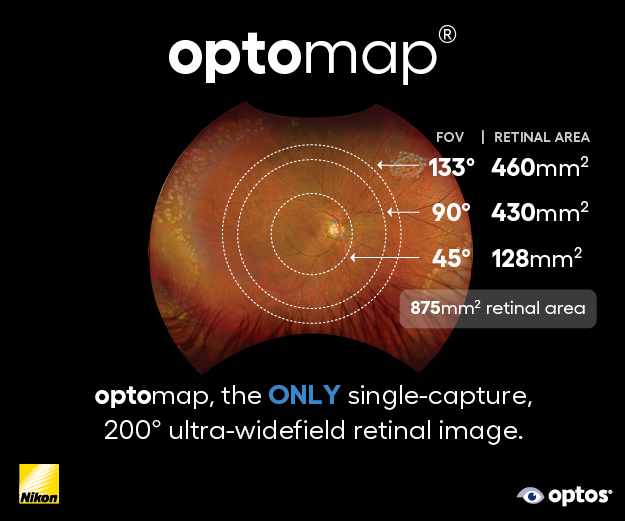

Case 1: Drusenoid PED resolution with RPE preservation

Drusenoid pigment epithelial detachments (PEDs) present a significant risk of progression to photoreceptor and RPE atrophy upon collapse.

Clinical presentation: A 60-year-old woman presented with large, central drusenoid PEDs in both eyes. Natural history data indicate that the resolution of such lesions is almost invariably accompanied by atrophy of the underlying RPE and overlying photoreceptors.

Response to therapy: Following PBM, one eye exhibited a remarkable anatomical response: the PED resolved and flattened, accompanied by a significant restoration of the ellipsoid zone on OCT. Crucially, this occurred without the expected RPE atrophy (See Fig 1 at the top of this article).

This structural success was matched functionally, with BCVA improving from 6/9 to 6/6. In the fellow eye, the PED remained structurally stable, yet she still achieved functional gain, improving from 6/30 to 6/24.

Clinical implication: This outcome suggests PBM may facilitate the metabolic clearance of sub-RPE deposits while sustaining cellular viability, potentially altering the typical course of PED collapse. Further cycles of PBM treatment and longitudinal follow-up will determine if her fellow eye eventually achieves a similar anatomical resolution.